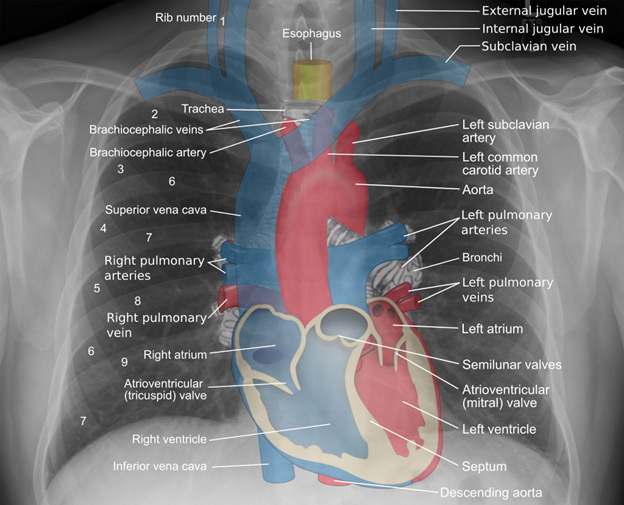

Blunt Cardiac Trauma

Blunt cardiac injury typically involves high speeds and decelerations to the chest wall, which usually results from motor vehicle collisions; however, it also can involve a range of mechanisms, from falls to crush injuries, direct blows with weapons, blast injuries, etc. Figure 3 is a diagram of the mediastinal structures outlined, and some structures will be covered in more detail with the associated injury in the setting of trauma.

Figure 3. Mediastinal Structures |

Imaging showing the mediastinal structures |

![]() |

Source: Mikael Haggstrom, MD https://commons.wikimedia.org/wiki/File:Mediastinal_structures_on_chest_X-ray,_annotated.jpg |